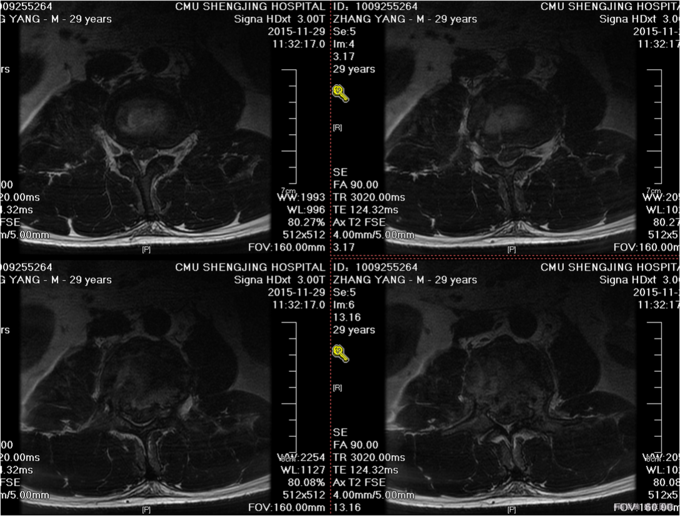

1.患者,青年男性,29岁,以“摔伤后腰部疼痛活动受限8小时”为主诉入院。 2.现病史:患者及家属述于2015-11-29晚2点左右奔跑过程中不慎摔倒,伤后意识稍有不清,唤之能醒,急送至我院急诊,行相关CT检查,提示腰2椎体及附件爆裂骨折,脊髓受压;腰1椎体、左侧横突骨折;骶1隐裂,我科以“腰椎骨折”为主要诊断收入院。患者病来无头晕头痛,无恶心呕吐,无腹痛腹泻,未排便排气.

专科查体:腰2椎体深压痛,叩击痛,双侧屈髋肌力4级,屈膝肌力5级,伸膝肌力5级,双足足趾肌力(L5,R5),左大腿内侧痛觉稍减弱,膝关节以下皮肤感觉正常,双侧足背动脉搏动可触及,末梢血运良好。 辅助检查:腰椎CT(2015-11-29):腰2椎体及附件爆裂骨折,脊髓受压;腰1椎体、左侧横突骨折;骶1隐裂

患者入院后,完善检查,明确诊断,患者于2015-12-01全麻下行腰椎后路,椎板减压,关节突植骨,椎弓根钉棒系统内固定术,术后给予患者抗炎,营养神经,止痛等对症治疗,患者病情好转后出院。